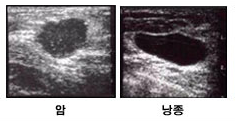

• 유방 초음파

종괴(멍울)의 성분이 양성 낭종(물혹)인지 고형 종괴인지 구별이 가능한 검사로 유방의 밀도가 높은 젊은 여성의 치밀 유방 등으로 유방 촬영시 잘 보이지 않는 종괴의 평가에 유용합니다. 또한 방사선 피폭이 전혀 없으므로 임산부나 수유부에게도 위험 없이 사용이 가능합니다. 종괴의 정확한 진단을 위해 필요한 경우 초음파를 보면서 동시에 조직검사를 시행할 수 있습니다. 검사 전 준비사항은 특별히 필요하지 않으며 검사대 위에 누운 후 젤리를 묻힌 감지기로 유방을 문지르면 검사기계에 영상이 나타나게 됩니다. 검사 후 부작용 및 주의사항도 없어 편안하게 검사 받을 수 있는 검사입니다.